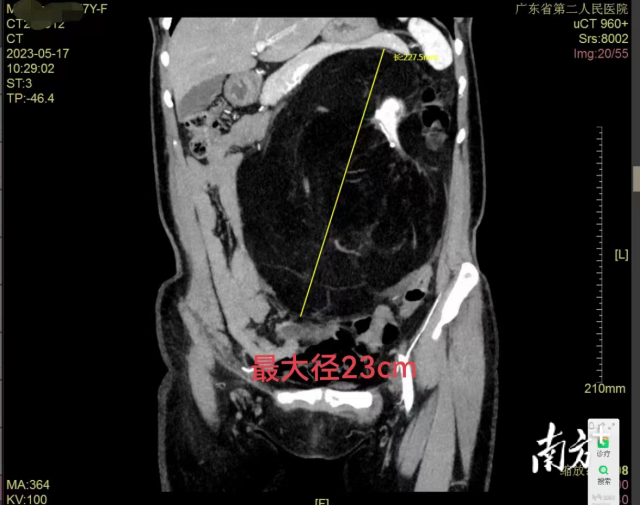

来自湖南岳阳的马阿姨今年57岁,半年前,因为腹部不适在当地医院检查发现腹部长了一个巨大的肿瘤,肿瘤包绕左侧肾脏、肾门血管,位置十分特殊。

邱晓拂主任为马阿姨安排了住院,并进行详细的检查,结合病史和影像,初步诊断马阿姨患的是左肾肿瘤,“虽说肿瘤良性可能性大,但肿瘤与左侧肾脏、左肾的血管关系极为密切,手术具有极大的挑战和难度。”